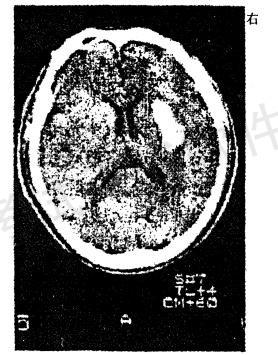

男性,56岁。高血压患者。旅游登山中突然左侧 肢体发麻、乏力。急送医院,摄头颅CT片如图

病损部位在A.左侧大脑皮质

B.右侧大脑皮质

C.左侧...